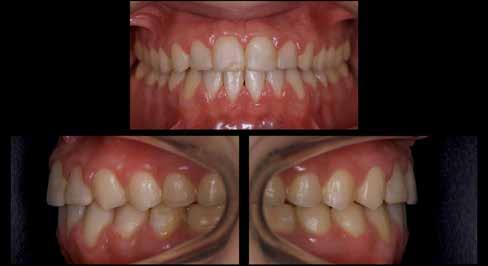

A fogászati kezelések során manapság már nem kizárólag az esztétikai megjelenés helyreállítására törekszünk. Sokszor a kedvezőtlen esztétikai megjelenés hátterében álló okok következményes módon a fogazat funkcionális működését is károsítják, így a kezelések során ezeknek a helyreállításával is foglalkoznunk kell. A különböző funkcionális és esztétikai diszkrepanciák kezelésére számtalan módszer létezik, ám ezen fogászati beavatkozások mindegyikében közös, hogy a kivitelezésük során nagyon szoros együttműködésre van szükség a kezelést végző fogorvos és a munkáját segítő fogtechnikus között. Az alábbi esetbemutatás során egy fiatal hölgypáciens fogazatának héjak alkalmazásával történő esztétikai és funkcionális rehabilitációját szeretnénk ismertetni.

sára is szükség van (2. és 4. ábra).

A 19 éves hölgypáciens azzal a kéréssel jelentkezett a rendelőnkbe, hogy szebb fogakat szeretne. Az első konzultáció alkalmával megkérdeztük, hogy mi zavarja leginkább a fogazatának jelenlegi megjelenésében, valamint azt is megbeszéltük vele, hogy milyen végeredmény elérése esetén lenne maradéktalanul elégedett. Ebben az esetben a kezelési célokat az alábbiakban határoztuk meg:

A páciens fogazata esztétikai megjelenésének és funkcionális működésének a lehető legtöbb, saját foganyag megtartása mellett történő helyreállítása (1. és 3. ábra).

A lehető legideálisabb esztétikai végeredmény elérése érdekében néhány esetben a fogak alakjának módosítá -

A kezelés megtervezése során kifejezett jelentősége van annak, hogy jó kommunikáció legyen a páciens, a fogorvos és a fogtechnikus között. A páciens leendő fogazatának természetes megjelenését a kezelésben részt vevő team szakmai felkészültsége, gyakorlati tapasztalata és a kezelés sikerességének irányába történő elkötelezettsége biztosítja. A beavatkozások megkezdése előtt megtörtént a páciens anamnézisének a felvétele, valamint a klinikai kivizsgálását is elvégeztük. Ezt követően lenyomatokat készítettünk a kiindulási állapotról, majd a kiindulási helyzetet extra- és intraorális fotók segítségével is rögzítettük (13. a-c. ábra).

A kezeléstervezés egyik legfontosabb lépése a mock-up elkészítése. A mock-up alapjául szolgáló wax-up-ot (felviaszolás) is ugyanolyan részletességgel kell a fogtechnikusnak elkészíteni, mintha azok már a végleges fogpótlások alapjául szolgáló mintázatok lennének. A mock-upnak nagyon pontosan kell illeszkednie, valamint a tervezett fogpótlás meg-

jelenését is rendkívül élethűen kell reprezentálnia. Ahhoz, hogy a páciens mock-uppal kapcsolatos első benyomásai kedvezőek legyenek, a mock-up színének a páciens „szemfehérjének” színével meg kell egyeznie. A kezelési cél páciens által történő elfogadása és a tervezett eredménnyel kapcsolatos „wow-effektus” kialakulása nagyban függ a páciensben az első megtekintés során kialakult első benyomásoktól.

Az eddigi tapasztalataink szerint a páciensek jelentős többsége egyértelműen kifejezi az elégedettségét, ha a mock-up megfelel az eredeti elképzeléseiknek. A bemutatásra kerülő esetben is ez történt. A tervezett végeredmény megtekintését követően a páciens azonnal kérte az általunk javasolt kezelési tervben ismertetett beavatkozások elvégzését. A héjak alapanyagául az Ivoclar Vivadent által gyártott A1-es színű Telio CS kerámiát javasoltuk. Az anyagválasztás hátterében az állt, hogy ez az anyag nagy keménységgel rendelkezik, valamint az, hogy a felszínét nagy simaságúra lehet polírozni. A páciens rendkívül fiatal életkora is azt a terápiás koncepciót erősítette, hogy a kezelés során lehetőség szerint kizárólag non-invazív beavatkozásokat alkalmazzunk.

A különböző terápiás lehetőségek bemutatása során a kezelésekkel járó lehetséges előnyök és hátrányok is ismertetésre kerültek.

A páciens már kezdetben is rendkívüli érdeklődést mutatott a preparálást nem igénylő (non-prep), héjakkal történő ellátással kapcsolatban. Ennek a terápiás modalitásnak az előnyei közé tartozik, hogy a fogakat egyáltalán nem, vagy csak minimál invazív módon kell preparálni, nincs szükség ideiglenes héjak készítésére, a héjak alapanyagául szolgáló kerámia nem hajlamos az elszíneződésre, nem jellemző a beavatkozások elvégzését követően jelentkező posztoperatív szenzitivitás, valamint hogy ezzel a módszerrel rendkívül kedvező esztétikai végeredményt lehet elérni. A fenti előnyök rendkívül meggyőzően hatottak a páciensre. A döntése során azt is figyelembe vette, hogy amennyiben ezeket a viszonylag költséges restaurátumokat választja, akkor ez a kezelés végösszegét is jelentős mértékben befolyásolja.

A kezelés során az jelentette a legnagyobb kihívást, hogy a héjakkal ellátott fogak élethűen utánozzák a természetes fogazat megjelenését. A fogpótlás színének, valamint a restaurátumok felszíni textúrájának és alakjának harmonikusan kell a páciens arcesztétikájához és karakteréhez illeszkednie.

A tényleges protetikai ellátás megkezdése előtt a páciens mosolygás közben látható fogait otthoni fogfehérítés keretei között a kérésének megfelelő A1-es fogszín eléréséig fehérítettük. A fehérítés során a későbbiekben héjakkal ellátásra kerülő fogak színén nem változtattunk. A fogak előkészítése részeként csupán a két felső nagymetsző (1.1,2.1) incizális élét kellett kismértékben redukálni. A többi felső front fog (1.3,1.2,2.2,2.3) nem került preparálásra.